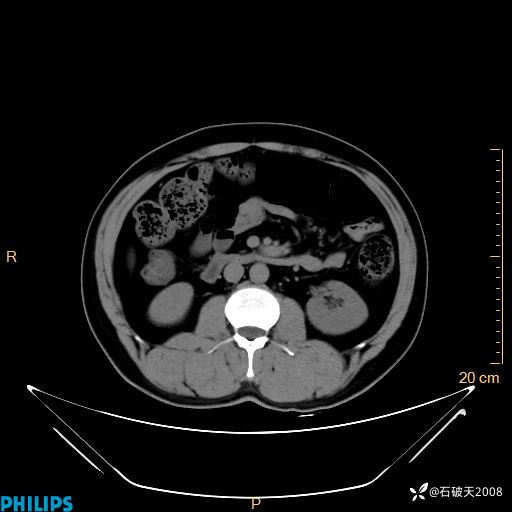

增强轴位